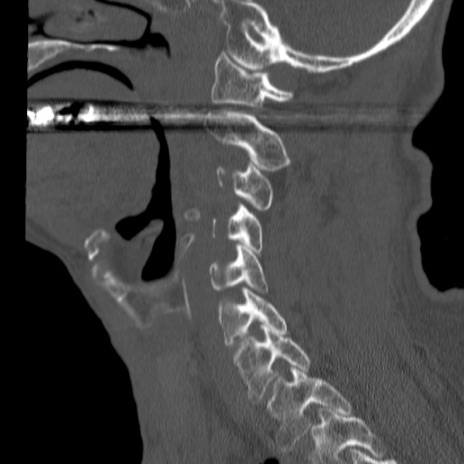

症例46 頚椎CT(矢状断像)

【症例】80歳代男性

【主訴】両側頚部〜上肢のしびれ

【現病歴】昨日、自宅内で転倒、その後より上記症状あり。意識障害なし。

【身体所見】両側上肢のallodynia(熱痛覚過敏)あり。MMTおよびDTRは正確な所見取れず。両上肢の挙上はなんとか可能。

異常所見と診断は?